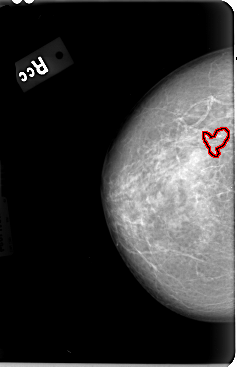

FILE: B_3030_1.RIGHT_CC.OVERLAY

TOTAL_ABNORMALITIES 1

ABNORMALITY 1

LESION_TYPE CALCIFICATION TYPE PLEOMORPHIC-FINE_LINEAR_BRANCHING DISTRIBUTION CLUSTERED

ASSESSMENT 4

SUBTLETY 3

PATHOLOGY BENIGN

TOTAL_OUTLINES 1

BOUNDARY